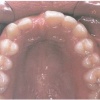

Ülemiste tsentraalsete lõikehammaste (intsisiivide) vahetumine. Retineerunud intsisiivid. Ülemised tsentraalsed esihambad lõikuvad orienteeruvalt 7-8-aastaselt. Enamasti lõikuvad samanimelised jäävhambad paaridena. Normaalne lõikumise järjekord 7, 5-aastselt: vt pilti